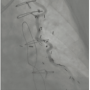

After a review of the angiographic images, we determined that the lesion in the LAD could not be visualized during native left coronary angiography (Figure 1). PCI of the LAD could not be performed through the LIMA due to its severe tortuosity (Figures 2 and 3).